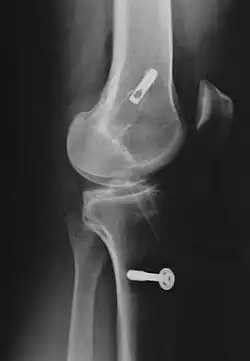

Treatments

Treatment of the unhappy triad usually requires surgery. An ACL surgery is common and the meniscus can be treated during the surgery as well. The MCL is rehabilitated through time and immobilization. Physical therapy after the surgery and the use of a knee brace help speed up the healing process. A typical surgery for a blown knee includes:

- Patellar tendon autograft (An autograft is a graft that comes from the patient)

- Hamstring tendon autograft

- Quadriceps tendon autograft

- Allograft (taken from a cadaver) patellar tendon, Achilles tendon, semitendinosus, gracilis, or posterior tibialis tendon

The goal of reconstruction surgery is to prevent instability and restore the function of the torn ligament, creating a stable knee. There are certain factors that the patient must consider when deciding for or against surgery.